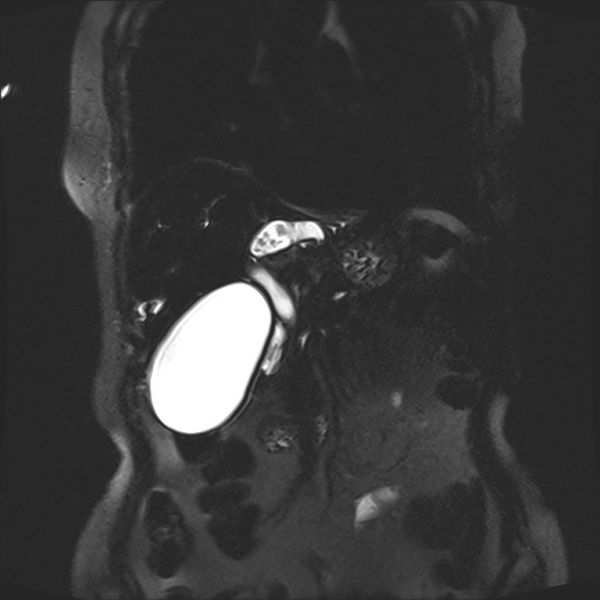

随着进一步检查的完善,患者诊断逐步明确:1.肝胆管结石(区域型), 2.胆囊结石伴胆囊炎, 3.胆总管结石伴梗阻性胆管炎。

术前影像学资料